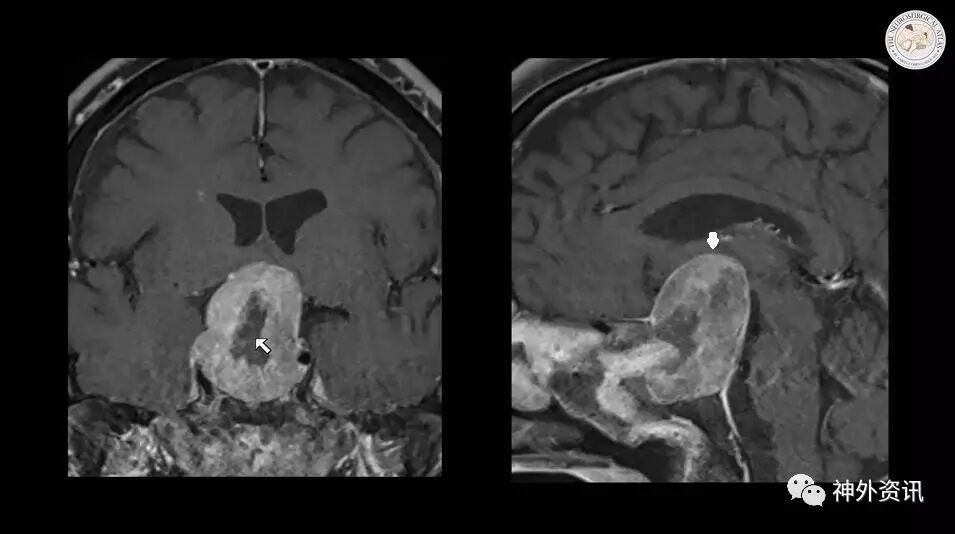

图7. 术后即刻MR。左图:可见肿瘤减压的范围(箭头),大部分肿瘤残留;右图:可见视交叉没有得到减压(箭头)。

2' - 3':And the closure was completed. Here is the extent of hemostasis. Immediately postoperatively, u can see the extent of my decompression. However, most of the tumor remains,and there is really no evidence of chiasmal decompression.

这是关闭(术腔)和止血的情况。术后即刻(MR)可见(肿瘤)减压的程度,但大部分肿瘤残留,视角叉没有得到减压。

I returned for the second stage of the operation about 4 days later. I thought that the timing between the two operations would allow the tumor to devascularized itself. And some of the tumor capsule will undergo necrosis and, lead to soft tumor, that can be easily deliverable.

4天后,再行二期手术。我认为两次手术间的(缓冲)时间会让肿瘤自行去血供,部分瘤囊会坏死,因此肿瘤质地会变软而易于“娩出”。